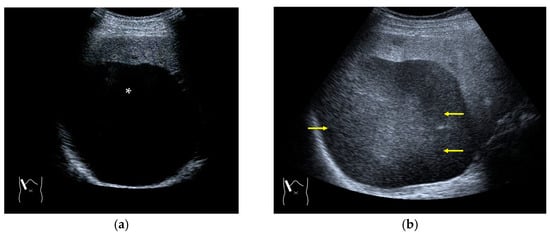

RAAs have recently attracted increased attention due to their increasing appearance when using recent high-end US equipment [42,43]. Although most operators encounter these artifacts in daily US examinations, they sometimes possess insufficient knowledge and feel diagnostic confusion with real structures, which is mainly because RAAs have seldom been described in the literature [42,43]. These artifacts are slightly more complex than the other B-mode artifacts. The composition of B-mode US images is based on the following assumptions: (i) the US beam passes along the same line path from the transducer to the target and back to the transducer and (ii) all received echoes come from the most recently transmitted pulse. Explaining the emission/reception of a pulse forms the basis for understanding RAAs. Assumption (ii) inevitably causes the following phenomenon: structures below the scanning depth appear in the US image when the echoes from deep structures detected with the first pulse return to the transducer after the second pulse has been emitted. The echoes coming from deep structures are, consequently, misinterpreted as having originated from the second pulse and are improperly displayed near the transducer (Figure 10). The easiest diagnostic strategy is to change the depth of the US image because this automatically changes the pulse repetition frequency (PRF) 4) [42,43].

Figure 10.

Range-ambiguity artifact in a hepatic cyst. (a) CEUS reveals a non-enhanced cyst (*) before the injection of the contrast medium. (b) Cloud-like echo (range-ambiguity artifact: RAA) appears in this hepatic cyst (arrows). (c) RAA disappears by changing the maximal depth of the view field. (d) Mechanism of RAA. When the PRF is high, the echo from the deep area is received during the second pulse’s receiving period and erroneously displayed closer to the transducer.